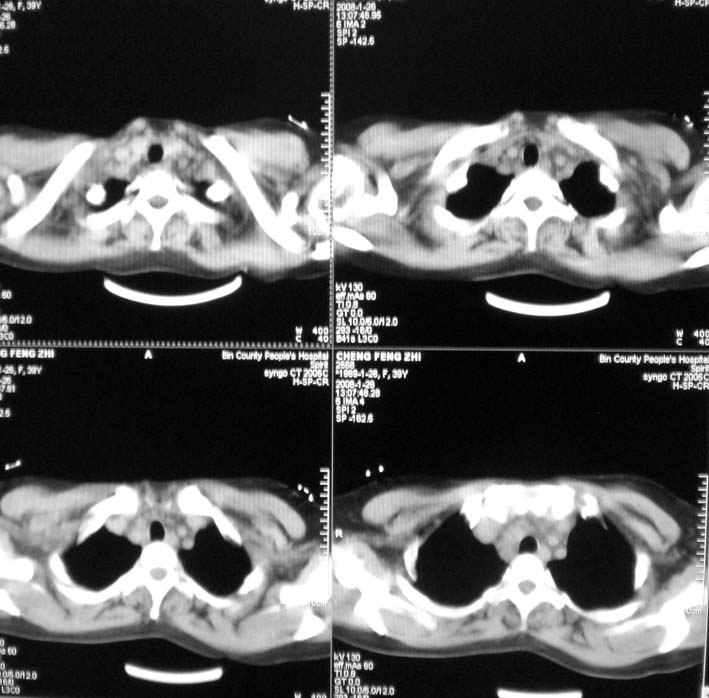

以下是引用guoke在2008-1-27 14:15:00的发言:[br]纵隔增宽,纵隔内血管境界不清,心包积液,考虑纵隔淋巴瘤.[br]

以下是引用随光逐影在2008-1-27 15:52:00的发言:[br]1)考虑为:淋巴瘤。建议:行进一步检查。2)心包积液。